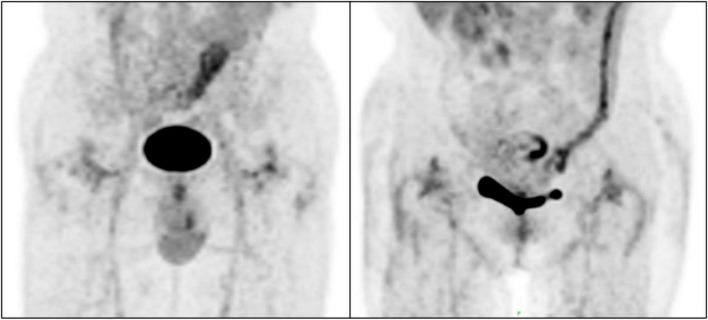

The aim of this study was to retrospectively analyze 18F-fluorodeoxyglucose (F-FDG) positron emission tomography (PET)/ computed tomography (CT) images of non-infected hip arthroplasty patients and summarize findings that may be useful for clinical practice.

F-FDG PET/CT images of non-infected hip arthroplasty patients were collected from September 2009 to August 2021. The region of interest was independently delineated by two physicians and maximum standardized uptake values (SUV) were recorded and compared. Serologic data were also collected and the correlation between SUV and serologic parameters was analyzed, while the images were classified based on the F-FDG uptake pattern in the images using the diagnostic criteria proposed by Reinartz et al. (9). The interval between hip replacement and PET/CT was classified by year and the characteristics of the two groups were compared. The images of patients who underwent PET/CT multiple times were analyzed dynamically.

A total of 121 examinations were included; six patients underwent PET/CT twice and two patients had three scans. There were no significant correlations between SUV and serologic results. The interobserver agreement between the two physicians in the classification according to the criteria of Reinartz et al. (9) was 0.957 ( < 0.005). Although there was non-specific uptake in cases with an arthroplasty-to-PET/CT interval this was non-significant. Additionally, F-FDG showed potential utility for dynamic observation of the condition of the hip.

SUV provided information independent of serologic results, meanwhile F-FDG showed potential applicability to the dynamic monitoring of hip arthroplasty-related diseases. However, the presence of blood vessels and muscles affected image interpretation and the specificity of F-FDG was not optimal. A more specific radionuclide is needed to maximize the benefits of using PET/CT for the assessment of periprosthetic joint infection (PJI).